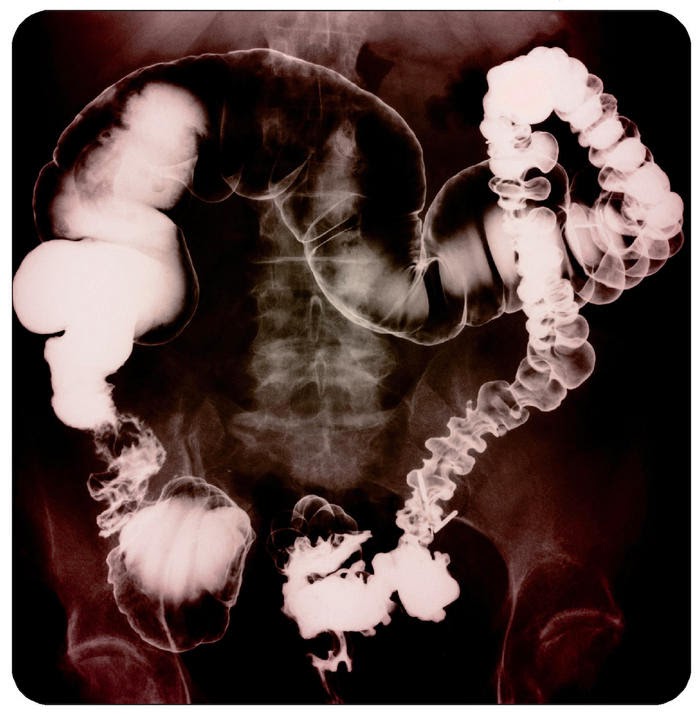

Es una enfermedad funcional digestiva crónica, benigna y recurrente de más de tres meses de evolución, caracterizada por malestar o dolor abdominal asociado a alteraciones del tránsito intestinal o distensión abdominal, sensación de evacuación incompleta, eliminación de moco con las heces y otros síntomas digestivos y extradigestivos, no atribuibles a otra enfermedad digestiva. El cuadro se presenta sin causas estructurales, metabólicas o infecciosas identificables.